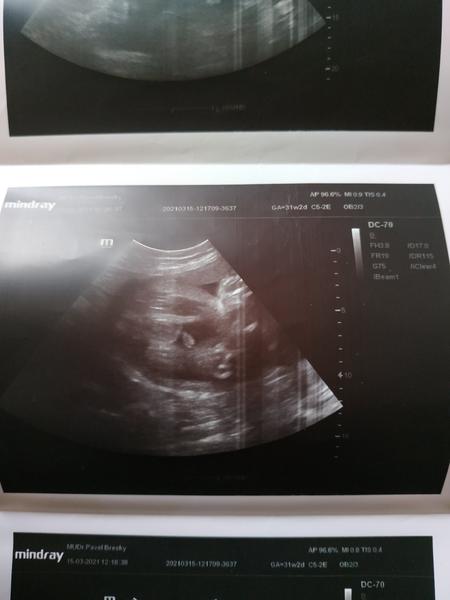

Dám ti sem pro představu moji fotku ze 3.screeningu, u mě 💯 kluk.